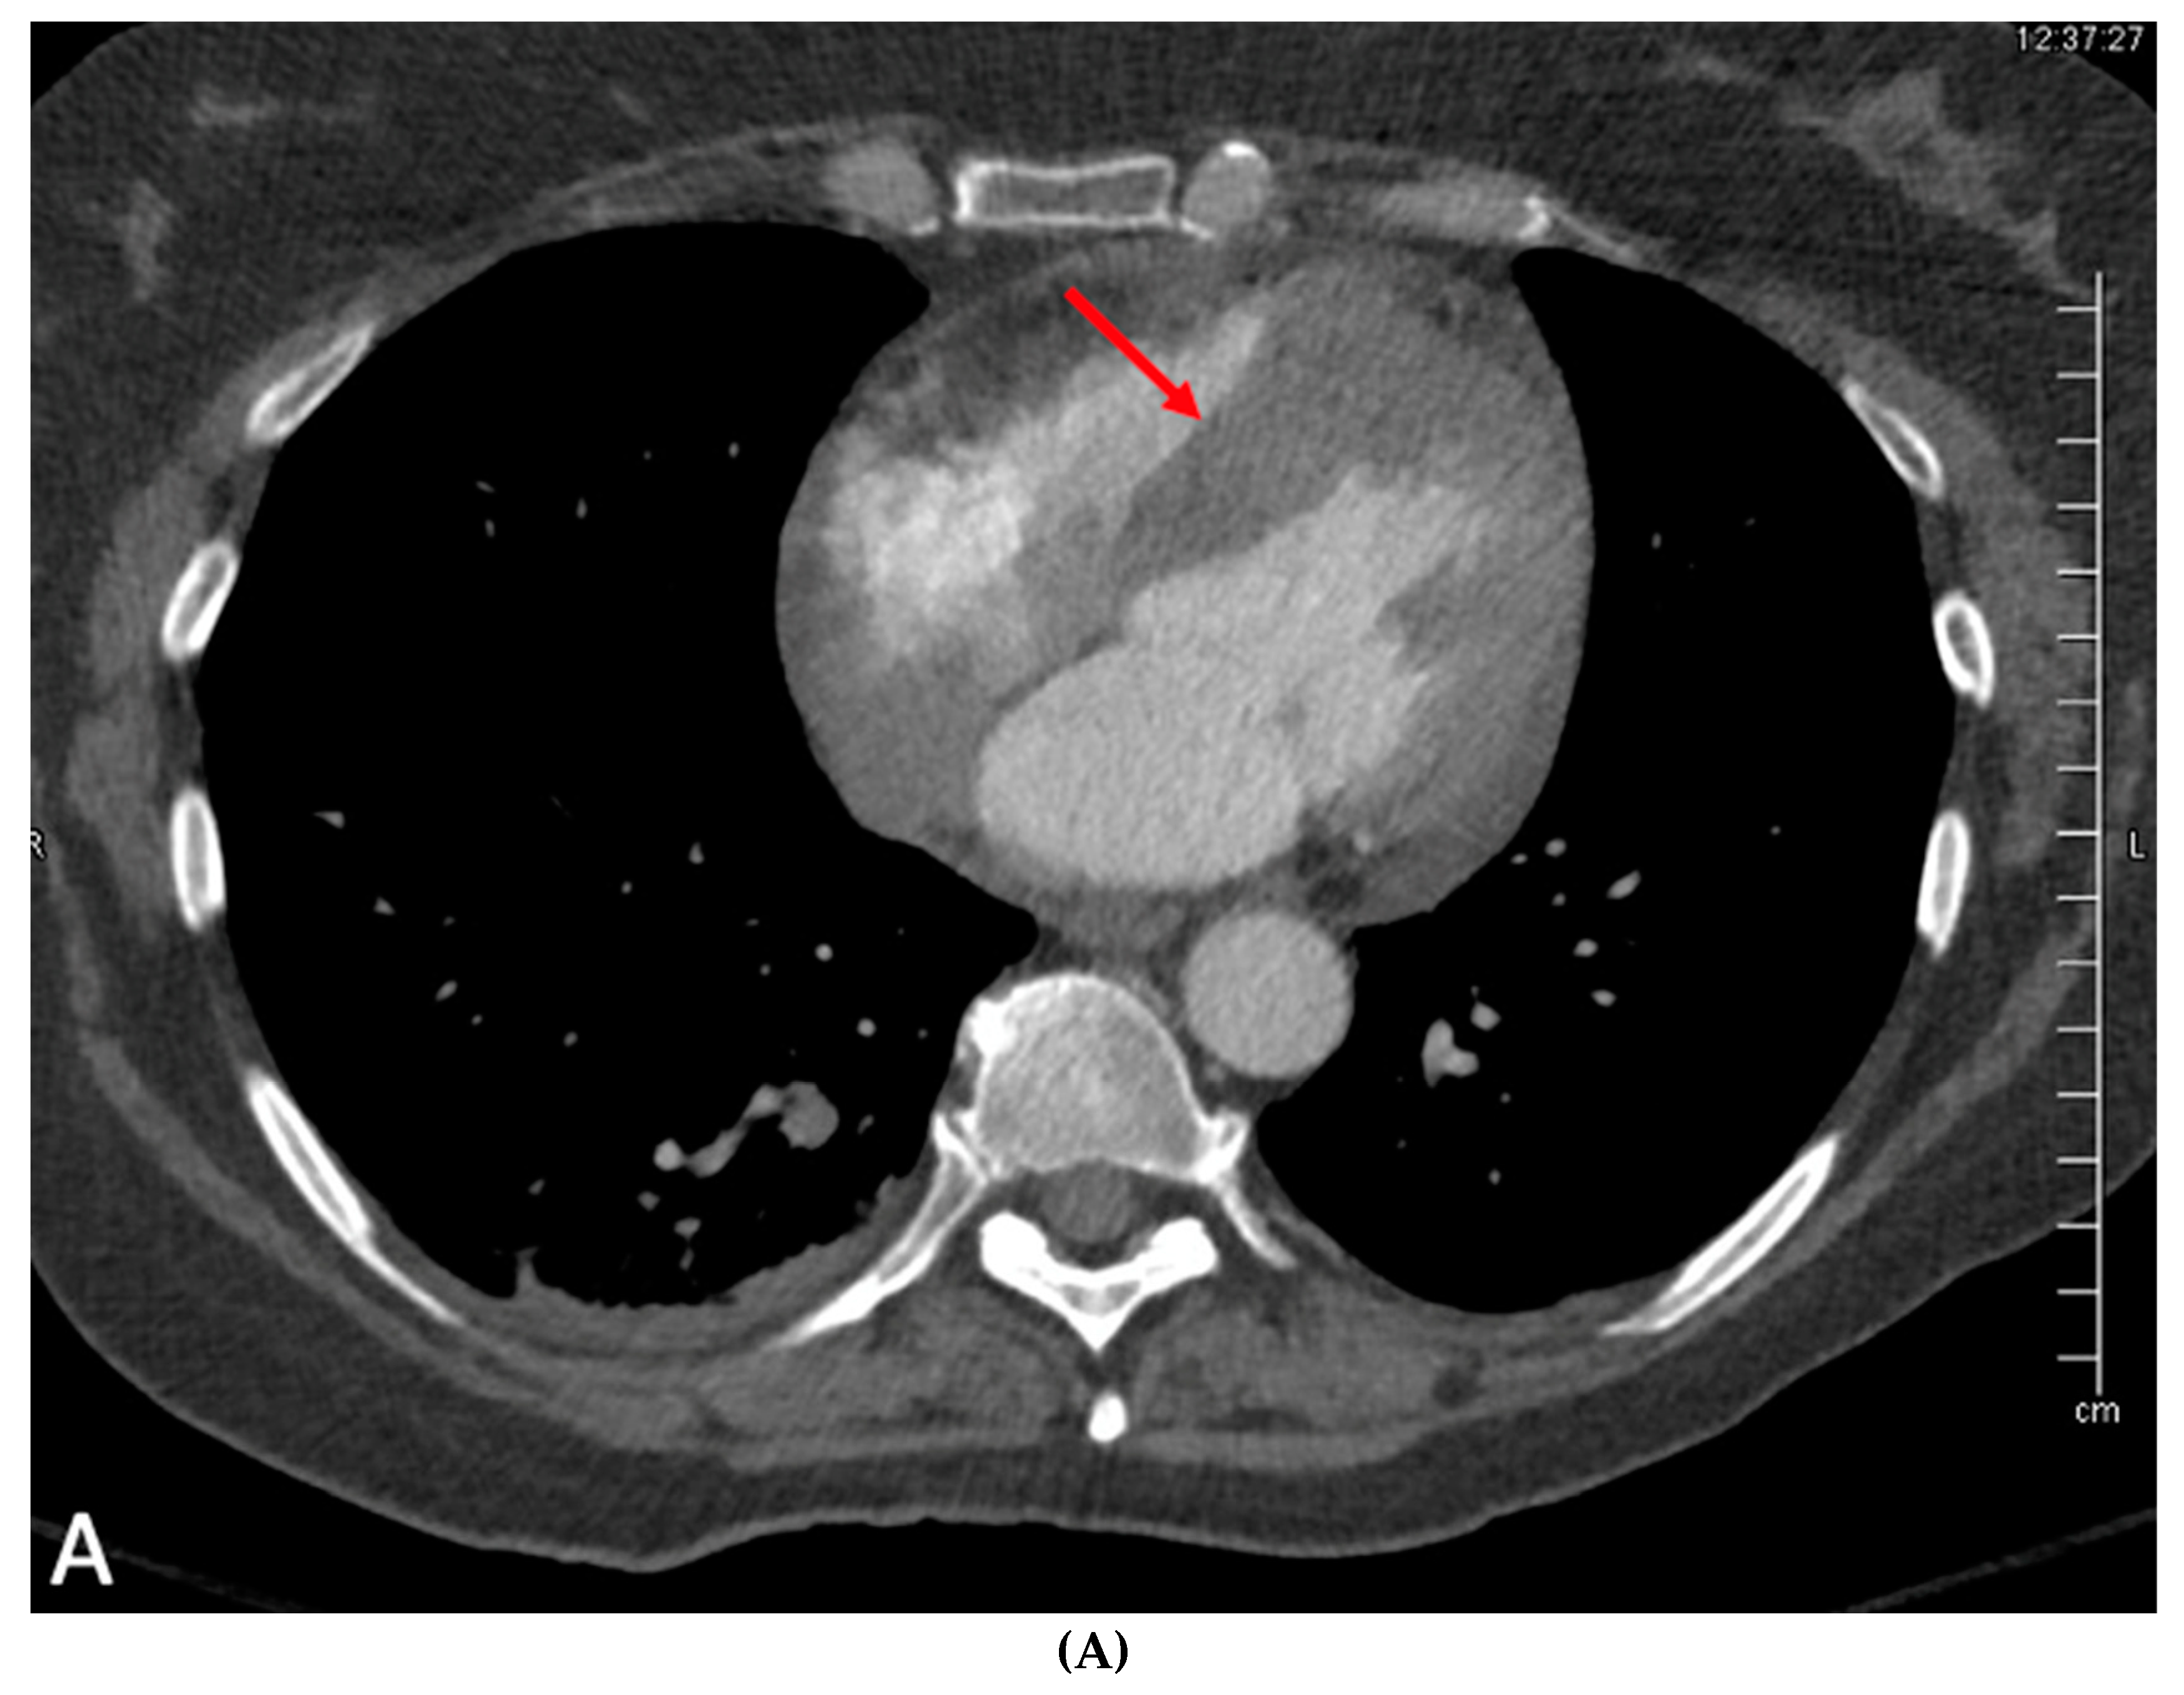

The angiographic findings suggested external compression as the likely cause of the 80% lesion in the mid LAD. This assumption gained credence when considering the non-invasive imaging results. Transthoracic echocardiogram showed normal left ventricular chamber diameter and systolic function with an ejection fraction of 50-55%, but was significant for notable septal wall thickening (Figure 3A–C). A subsequent PET/CT scan demonstrated an FDG-avid focus aligning with a heterogeneously enhancing mass along the interventricular septum of the heart, measuring approximately 3.1 x 2.8 cm, representing a significant change from her previous scan (Figure 4A,B). A post-procedural CT scan, performed after the emergent coronary angiogram and pacemaker implantation, revealed significant interventricular septal thickening corresponding to myocardial metastases (Figure 5A), a contrast to a CT performed approximately five months prior, which indicated normal septal thickness (Figure 5B).

Figure 4. A: Positron emission tomography with fluorodeoxyglucose (FDG) uptake in the interventricular septum (red arrow) consistent with metastases from known cervical cancer, correlating with TTE findings above. B: Prior PET (3-4 months prior).